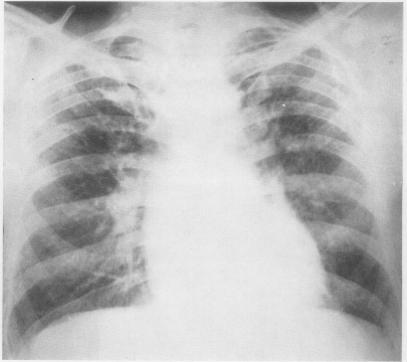

In assessing patients suffering from farmer's lung, the acute stage must be distinguished from the chronic stage of the disease. The conspicuous radiographic signs in the acute farmer's lung episode and the often dramatic clearing make an important contribution to the diagnosis. The radiographic changes in chronic farmer's lung are not specific and cover a wide range of appearances. Even minor nodular changes are significant. Farmer's lung, acute and chronic, is not a disease predominantly characterized by a defect in gas exchange. During the acute illness the reduction in diffusing capacity is often accompanied by a decrease in lung volumes; the pulmonary function profile of the chronic stage is variable. In only a relatively small proportion of chronic farmer's lung patients does a defect in gas exchange predominate, and in some it may be manifest only during exercise. Airway obstruction is a feature of chronic farmer's lung. In chronic farmer's lung patients discrepancies between the severity of complaints and results of pulmonary function tests are not infrequent. In some patients with considerable disability conventional pulmonary function studies may demonstrate little or no impairment of the functions measured. In patients suffering from an acute farmer's lung episode, serological tests should be positive, possibly in high titre. In the chronic stage of the disease the chance of finding positive serology in a patient diminishes with the length of time elapsed since the last acute episode. The period of serological transition appears to be the third year.